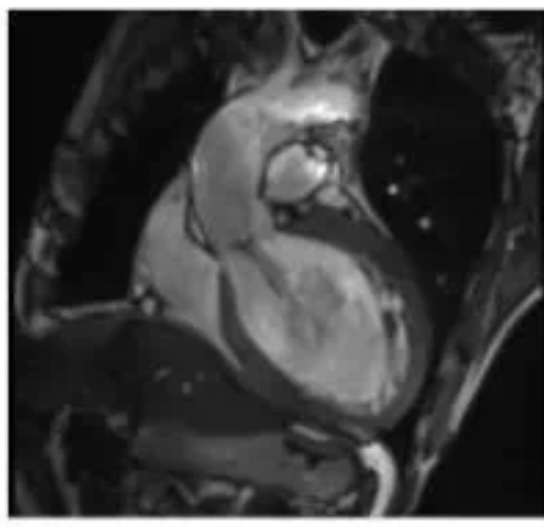

6、心臟CTA、MRI成像技術(shù);

6、心臟CTA是經(jīng)靜脈注射造影劑后進(jìn)行CT快速掃描和圖像重建技術(shù)獲得冠狀動(dòng)脈圖像,以精準(zhǔn)了解冠狀動(dòng)脈是否存在解剖變異、畸形、心肌橋、狹窄,評(píng)估冠狀動(dòng)脈支架或搭橋術(shù)后血管情況等。心臟磁共振檢查具有無(wú)輻射、多參數(shù)、多平面、多序列成像等特點(diǎn),具有良好軟組織分辨力,一次檢查可獲得心臟解剖形態(tài)、心臟功能、血流、心肌灌注或活性、心臟代謝、大血管和冠狀動(dòng)脈的信息,在診斷心肌病方面具有重要意義。

心臟冠脈成像 VR

心臟瓣膜病